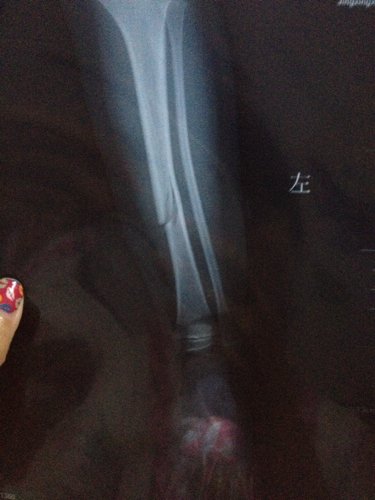

三周岁宝宝小腿胫骨青枝骨折,到医院医生没有复位直接打了石膏,但一个月去拆石膏拍片子还是有明显裂缝有影响吗?还有孩子什么时候可以下地负重,医生说拆石膏就可以下地,但是我看片子还是裂缝所以没敢让孩子走,正骨得人说得两个半月,现在看她得腿是没事动来动去挺自然。就是下地不敢使劲。请各位医生高手帮忙看看,下面的两张片子分别是刚碰着和一个月后得。非常感谢!!